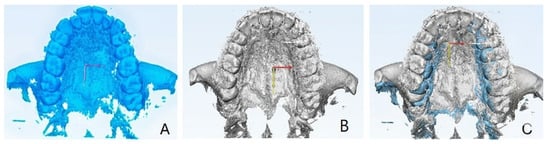

2.9.1. Qualitative Evaluation of Maxillary Expansion on Cone Beam Computed Tomography

3.2. Qualitative Evaluation of Maxillary Expansion on Cone Beam Computed Tomography

3.3. Quantitative Two-Dimensional Analysis of Upper Palatal Expansion on CBCT

3.4. Evaluation of Dental Effects: Palatal Alveolar Angle, Buccal Tipping Angle, Bone Dehiscences and Fenestrations